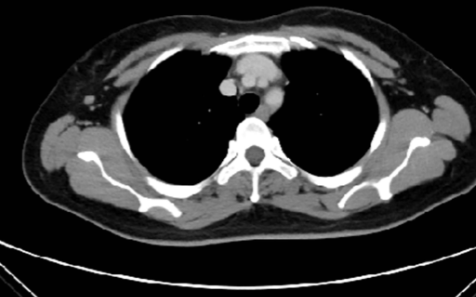

Preoperative identification of axillary lymph node metastasis can play an important role in treatment selection strategy and prognosis evaluation. This study aimed to establish a clinical nomogram based on lymph node images to predict lymph node metastasis in breast cancer patients. A total of 193 patients with non-specific invasive breast cancer were divided into training (n = 135) and validation set (n = 58). Radiomics features were extracted from lymph node images instead of tumor region, and the least absolute shrinkage and selection operator logistic algorithm was used to select the extracted features and generate radiomics score. Then, the important clinical factors and radiomics score were integrated into a nomogram. A receiver operating characteristic curve was used to evaluate the nomogram, and the clinical benefit of using the nomogram was evaluated by decision curve analysis. We found that clinical N stage and radiomics score were independent clinical predictors. Besides, the nomogram accurately predicted axillary lymph node metastasis, yielding an area under the receiver operating characteristic curve of 0.95 (95% confidence interval 0.93-0.98) in the validation set, indicating satisfactory calibration. Decision curve analysis confirmed that the nomogram had higher clinical utility than clinical N stage or radiomics score alone. Overall, the nomogram based on radiomics features and clinical factors can help radiologists to predict axillary lymph node metastasis preoperatively and provide valuable information for individual treatment.